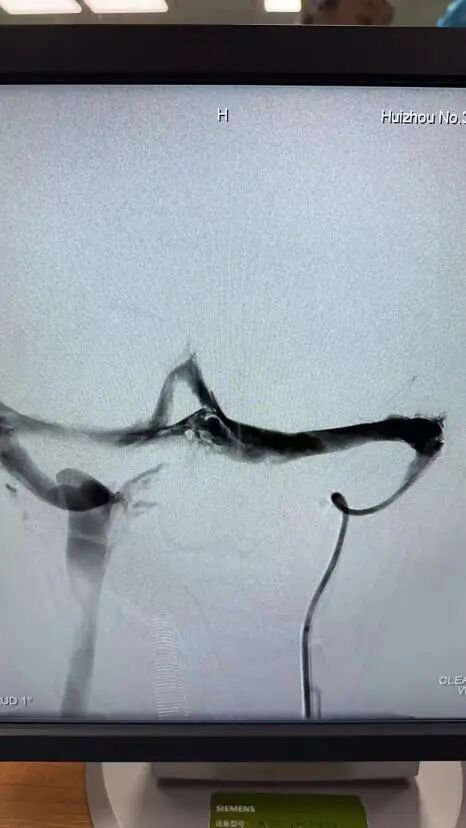

在充分準備后,景英朝治療團隊在麻醉科、介入導管室等多學科密切合作下,順利為患者行“顱內靜脈竇取栓術+腦靜脈竇溶栓術”,成功開通了阻塞的大腦靜脈及靜脈竇,患者轉危為安。

左頸總靜脈造影→左側橫竇血栓→完全再通